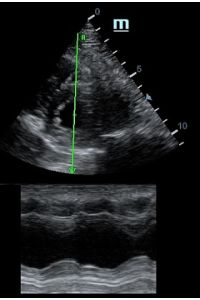

MAPSE - амплитуда движения латерального кольца митрального клапана, позволяет рассчитать фракцию выброса по формуле EF = 4.8 × MAPSE (mm) + 5.8, очень быстрый и гораздо более точный («прародитель Strain») метод чем широко распространенный метод Teicholtz. В современных приборах можно легко добавить свою формулу при отсутствии ее в стандартном калькуляторе. Главным условием является проведение линии М-режима параллельно стенке левого желудочка в апикальном четырехкамерном сечении, что легко достигается при использовании функции Free Xros.